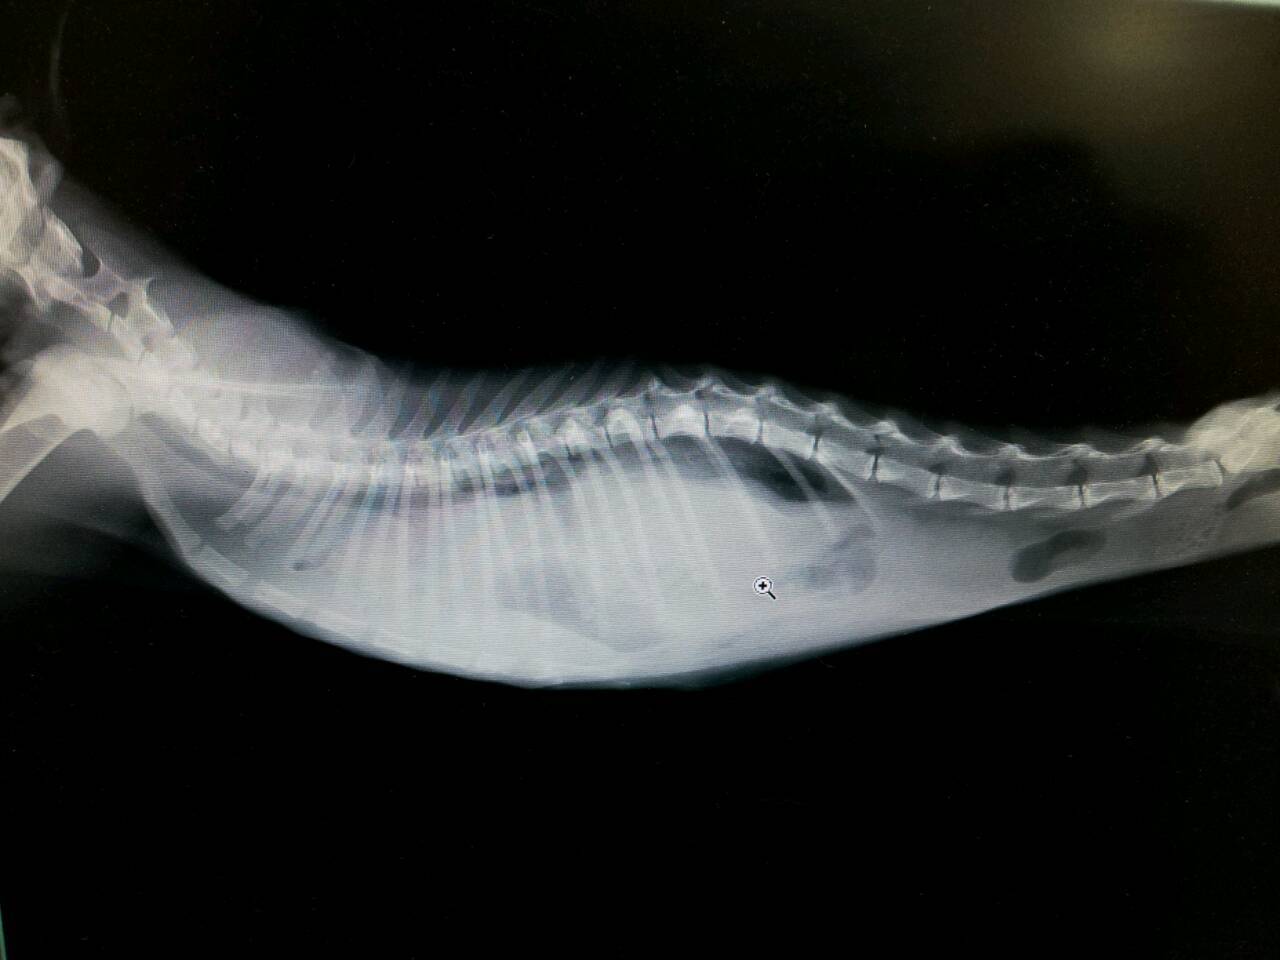

阿福已3個月大,但全身脫水嚴重,皮膚拉起完全無法彈回原狀,加上長期營養不良皮包骨,救援時只有700g。照了x光片發現他橫隔膜疝氣,已完全看不出肺臟,沾黏十分嚴重,且左後腳骨折,反射不良,亦需治療。

11/11阿福經連日來打皮下點滴,脫水情況、精神和喘氣的狀態都比先前好,體重亦回復到1.2公斤,麻醉上較安全,阿福所有器官都擠到肺臟,拖越久沾黏越嚴重,只會增加手術困難,故醫師評估後決定本日動刀。因為器官都跑到胸腔、要一個個歸位,腹部開的傷口很大,連胸骨都剪開,加上沾黏有點嚴重,手術困難,4個多小時天快亮才結束,故後腳骨折的手術這次沒有一起動刀,視貓咪恢復狀況、長大健康些再擇期動手術。